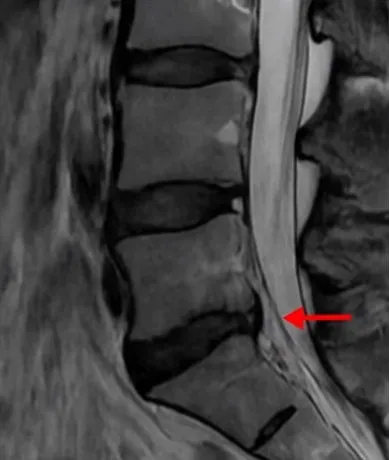

디스크내장증은 디스크가 튀어나오지 않았음에도 허리와 골반에 묵직한 통증을 유발하는 질환으로, 진짜 원인은 디스크 손상이 아니라 허리 근육 기능의 약화와 근 기능 이상이다.

의학계 다수는 디스크내장증을 공식 질환으로 인정하지 않으며, 블랙디스크도 통증의 직접 원인이 아니라는 주장이 제기된다. 신경주사나 신경성형술은 디스크내장증에 효과가 없거나 일시적이어서 무분별한 시술로 이어지기 쉽다.